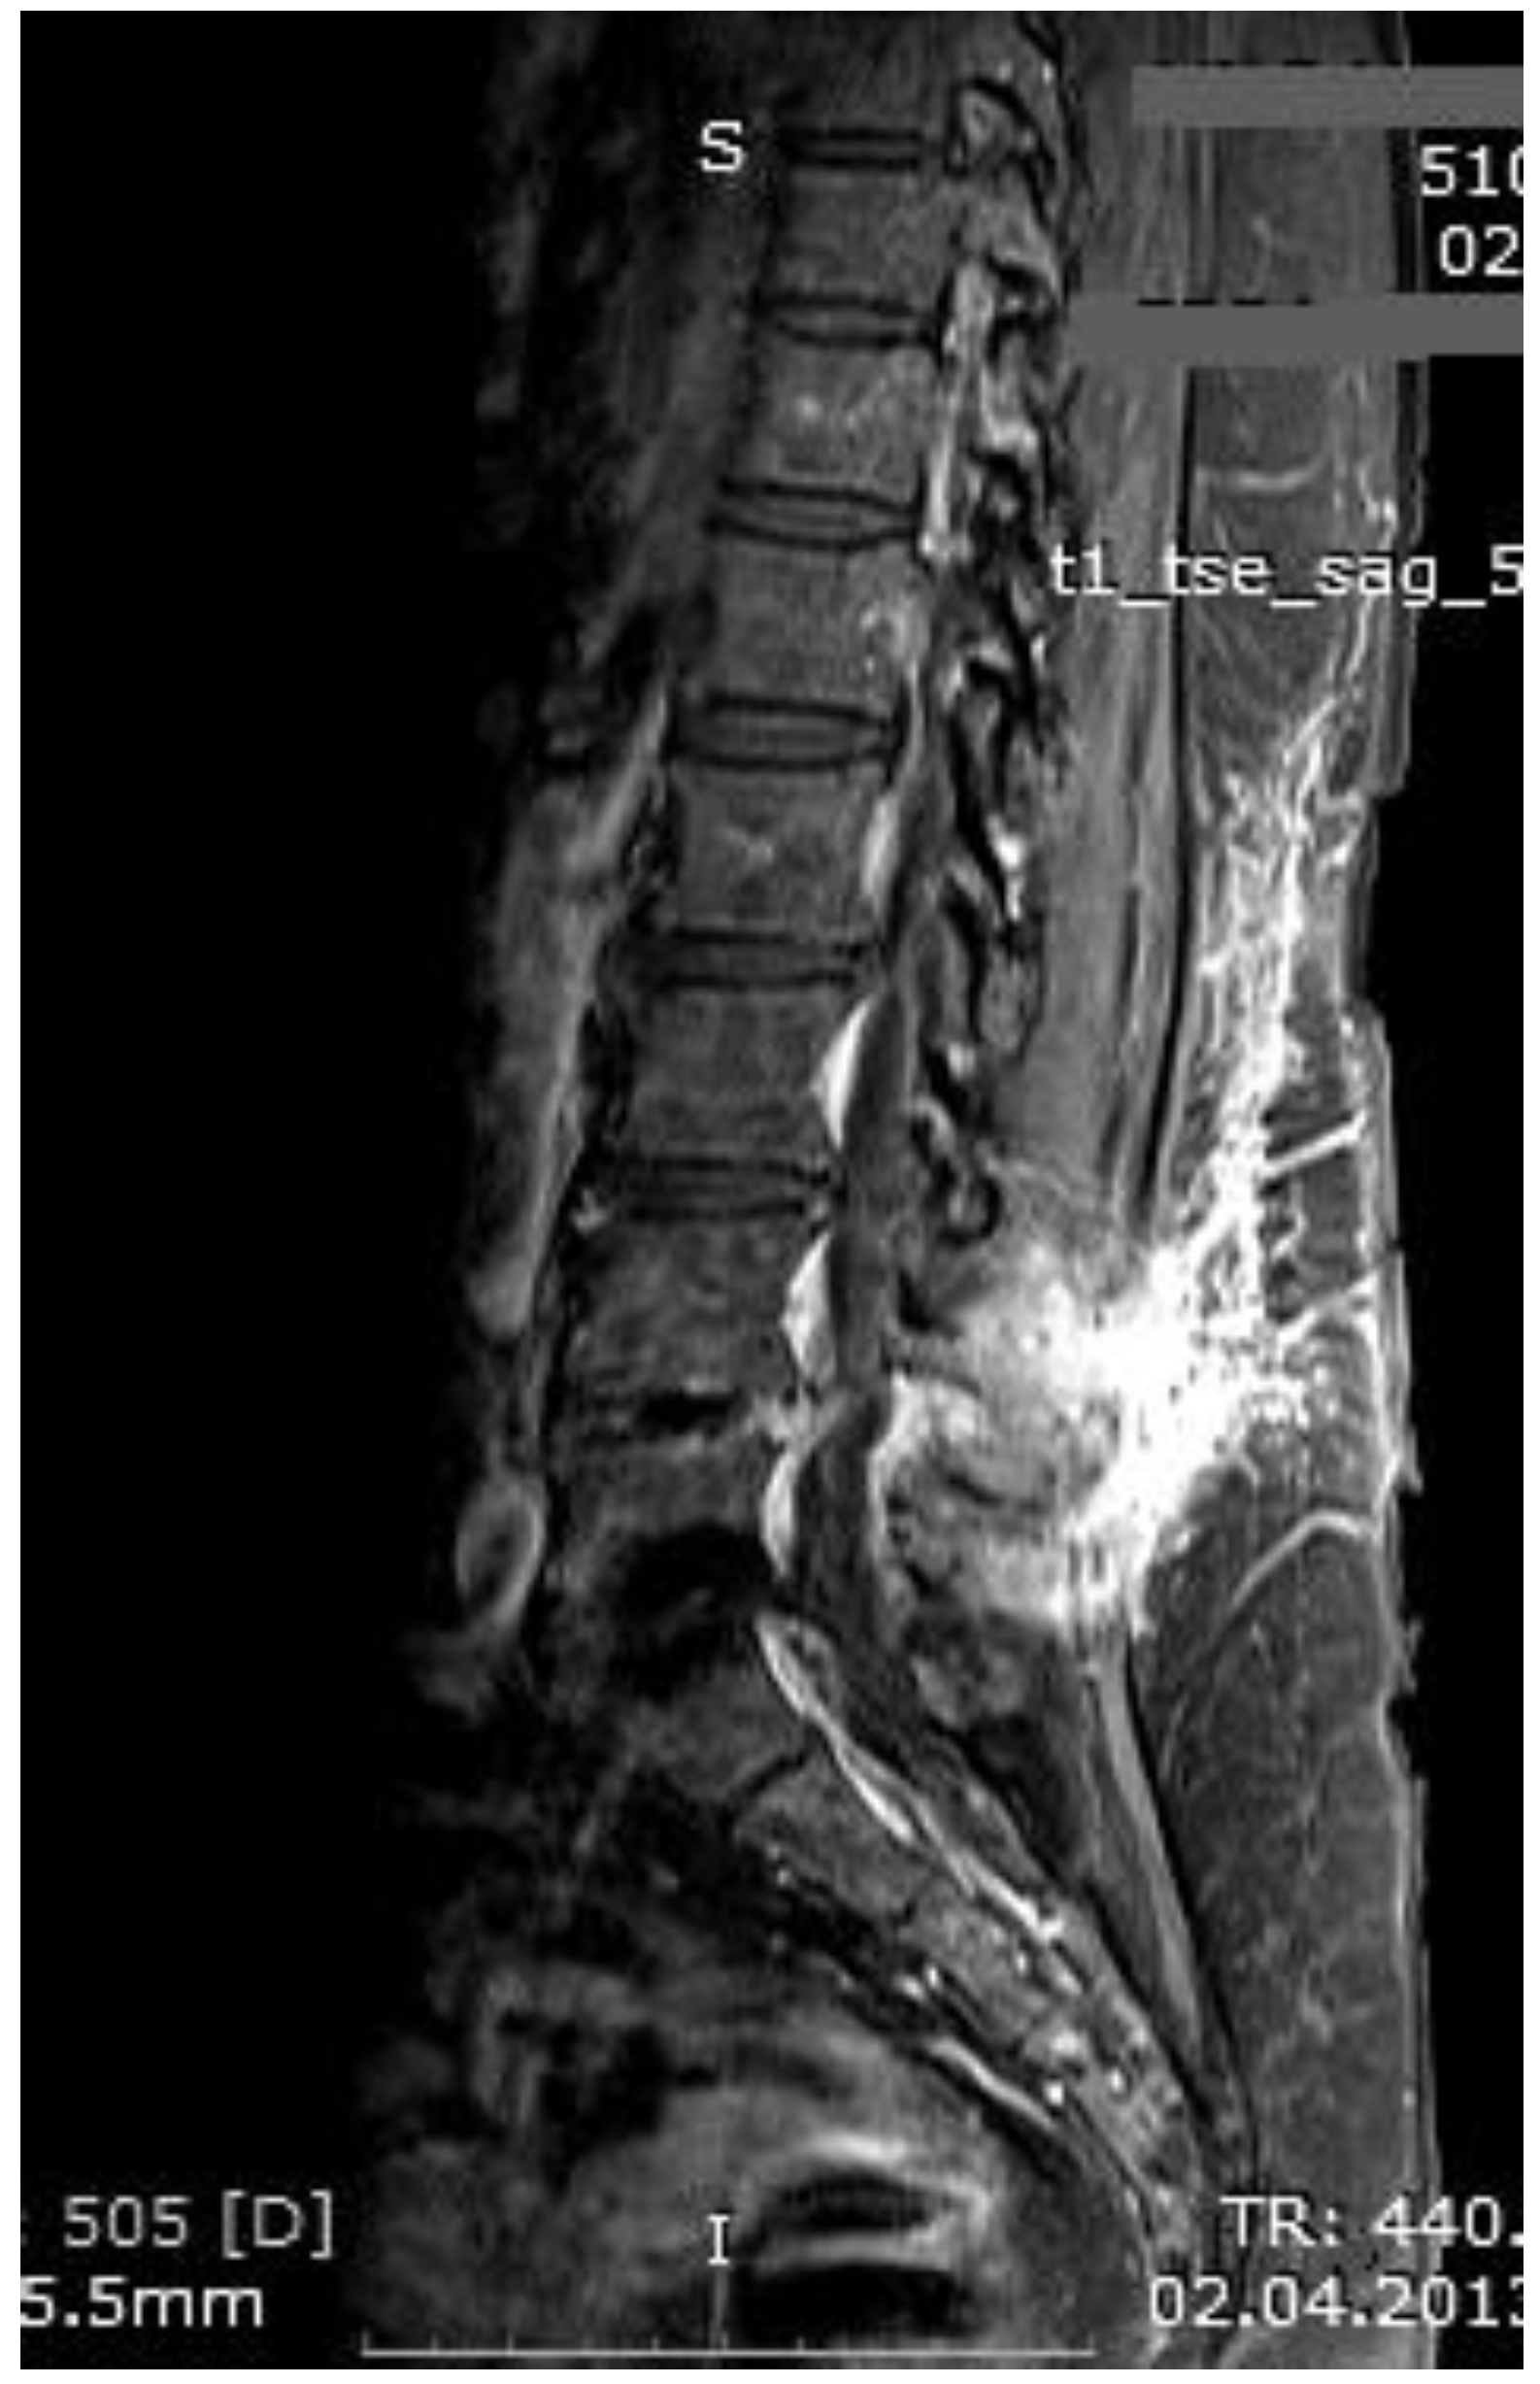

Figure 3. MR imaging T1-weighted scan showing inflammatory infiltrates in the course of pre-HBO2 treatment.

The mean number of total HBO2 sessions was 33 (±18.5) sessions. The HBO2 treatment was tolerated well by all patients except two. One patient had to receive analgesics (non-steroidal anti-inflammatories) before HBO2 sessions because she had severe back pain, and in one patient the treatment was interrupted for five days because of minor middle ear barotrauma. Improvements in clinical evaluations and laboratory findings were observed in all cases at the end of the HBO2 therapy. The mean erythrocyte sedimentation rate (ESR) value reduced from 76.1 (range, 6–129) to 45.7 (range, 5–81) mm/h, and the mean C-reactive protein (CRP) concentration reduced from 82.9 (range, 14–202) to 17.5 (range, 1–49.5) mg/L (normal limits; ESR: <20 mm/h, CRP: 0–5 mg/L). Infection resolution was adequately achieved in 12 of 13 patients on MR imaging at the end of HBO2 treatment or during the first month of follow-up (Figure 3, Figure 4 and Figure 5). There was no significant improvement in one patient. To extend the total clinical follow-up period up to three years (mean: 11 months; range, 1 month–3 years), telephone interviews were conducted to determine any recurrence of symptomatic clinical infection. No recurrence of infection, spinal instability, or deformity was seen in any patients.